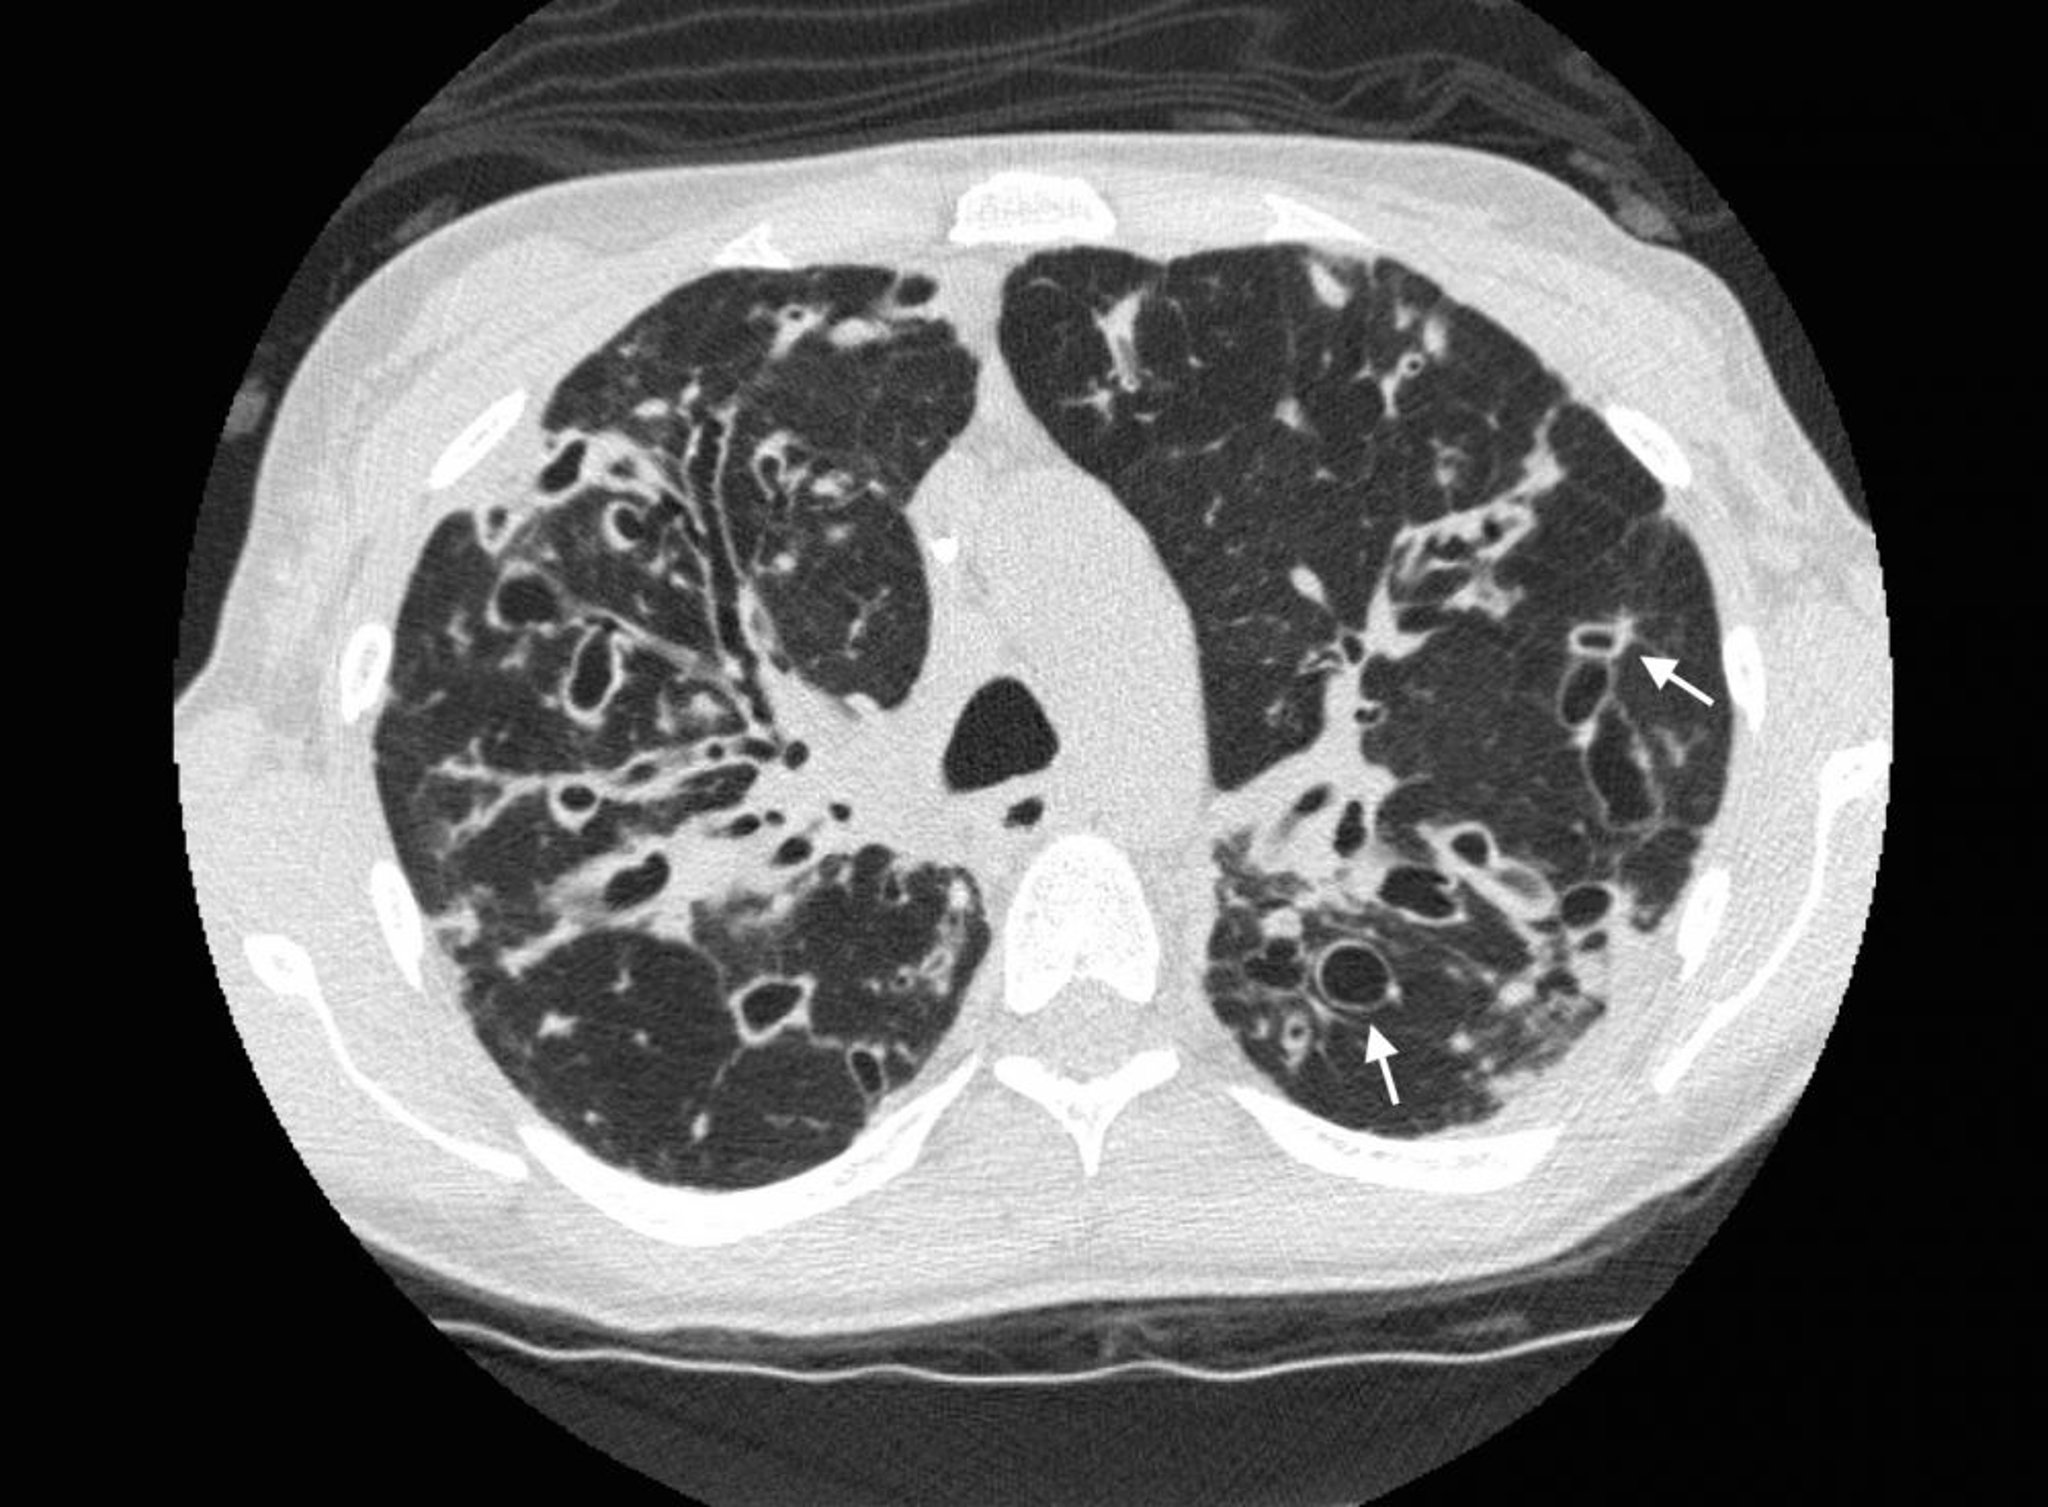

A TC de alta resolução é a modalidade de exame de imagem de escolha para diagnosticar definitivamente, bem como definir a extensão da bronquiectasia. Achados típicos da TC incluem dilatação das vias respiratórias (em que o lúmen interno de 2 ou mais vias respiratórias excede o diâmetro da artéria adjacente) e o sinal de anel de sinete, em que uma via respiratória dilatada e espessada aparece adjacente a uma artéria menor na incidência transaxial. A ausência do afilamento brônquico normal pode resultar em brônquios de médio calibre visíveis estendendo-se quase até a pleura. "Sinal do trilho de trem" pode ser facilmente visível na TC e é indicativo de paredes das vias respiratórias dilatadas e espessadas (linhas paralelas) preenchidas com muco.

Como os danos às vias respiratórias pioram ao longo do tempo, as alterações bronquiectásicas progridem de achados cilíndricos a varicosos e então a achados císticos nas imagens. Atelectasia, consolidação, tampões mucosos e diminuição da vascularização são achados inespecíficos.